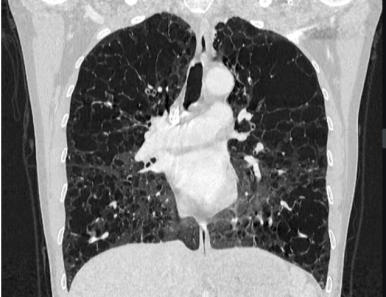

■ Cystic lesion (낭성 폐병변)

§ Cystic lung disease

- 공기를 포함한 투명한 공간 (air - containing lucency)

- 벽은 거의 식별할 수 없을 정도로 얇음 (thin wall)

- Lymphangioleiomyomatosis

→ distal airways에서 Smooth muscle의 증식으로 인해 발생하는 질환

→ diffuse thin wall cysts, 고전적으로는 유미(chylous) effusion과 동반